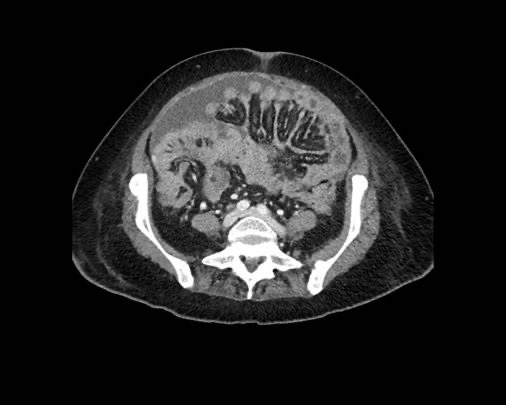

Cuộn xem ảnh CT

Ca lâm sàng 1

Cuộn qua các lát cắt.

Bạn có thể phát hiện tất cả các tổn thương cấy ghép phúc mạc không?

Bệnh nhân này đã được phẫu thuật và toàn bộ phúc mạc được ghi nhận phủ kín bởi các tổn thương u dạng kê.